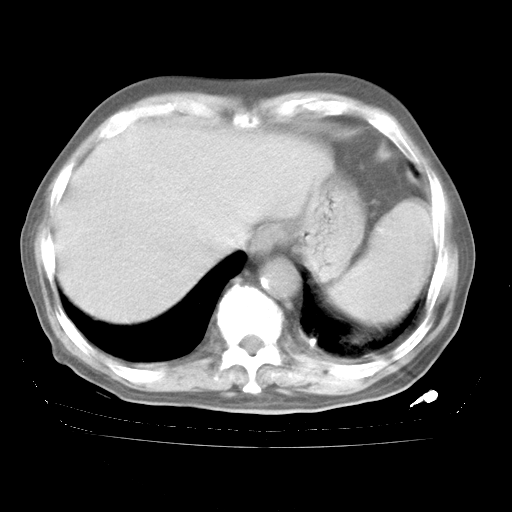

4月28日肺部CT——再次出现类似去年5月9日——透光度降低,“间质性”改变。

4月28日肺部CT

个人阅读4.14日肺部CT平扫:纵隔窗无异常,但肺窗示:双下肺内、后基底段有片絮状侵润影,部位以后基底段为著,以间质改变为主,呈急性肺泡炎征像,和首次住院影像学有相似之处。仅是个人读片,明日请相关专家再读片哈。其它建议同上。

1、108#的是4月14日的胸部CT(发此贴时还没看着28日的CT)。14日的胸部CT其实已经出现改变(如108#所述),个人认为28日的胸部CT除纵膈窗疑似有双侧胸膜增厚或少量胸积液(可行胸部B超明确)外,与4月14日对照病变有所加重;2、已经给予“异烟肼、利福平、乙胺丁醇”抗痨治疗?如果是,甲强龙80mg可缓慢减量;如果环磷酰胺已停用,暂不使用;3、中性粒细胞92%,明显升高,目前体温情况?注意合并细菌感染可能,使用左氧氟沙星情况下,是否联用B-内酰胺类抗菌药物?另外是查免疫全套非风湿全套。